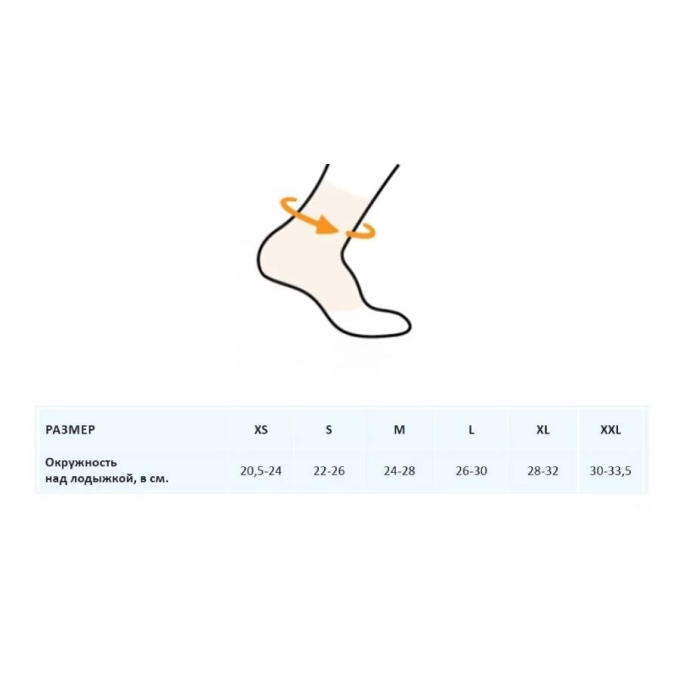

Арт: ГС-645

Бандаж на голеностопный сустав со вставками ГС-645

Арт: ГС-648

Бандаж на голеностопный сустав с дополнительной фиксацией ГС-648

Арт: ГС-654

Бандаж на голеностопный сустав разъемный ГС-654